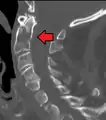

Position of axis (shown in red) | |

Its shape and position (shown in red) from above. The skull is shown in semi-transparent.

Its shape and position (shown in red) from above. The skull is shown in semi-transparent. Axis seen from above